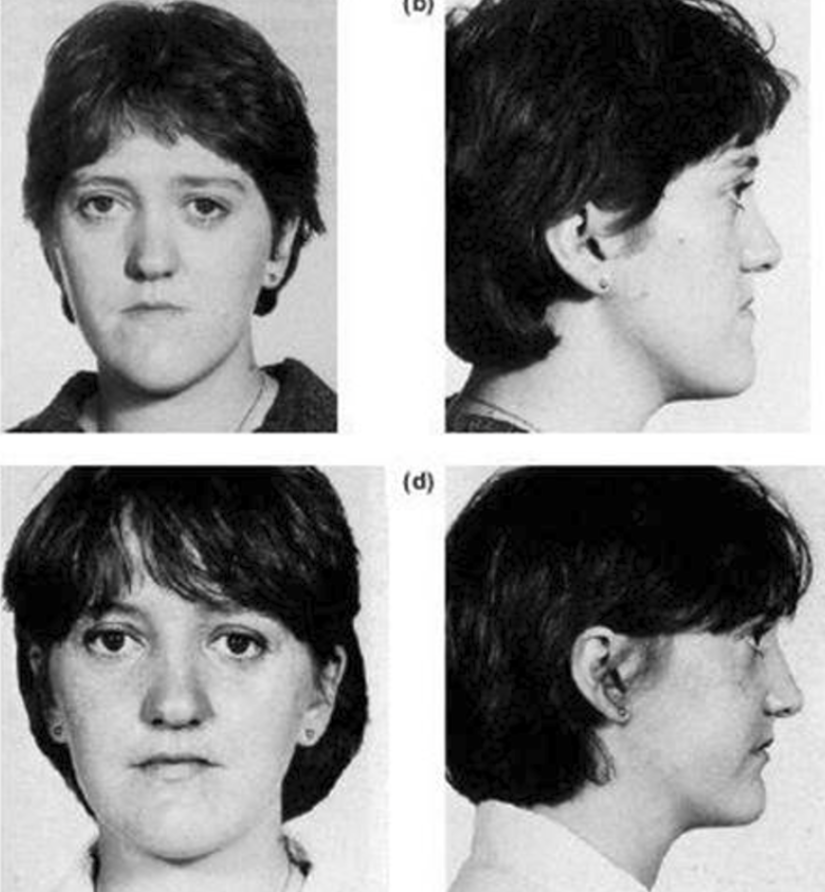

- The case below fits the criteria, the patients ANS and nose was fine in proportion to the rest of the face, but the maxilla sat almost vertical with little to none anterior facial depth. Advancing the lefort 2 block gave the missing anterior depth and transformed her frontal view.